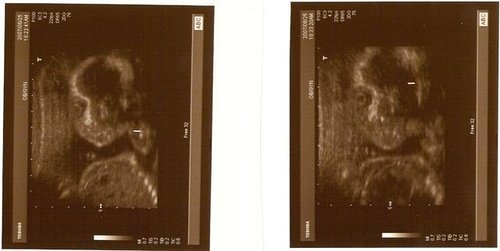

當過媽媽的都知道這是什麼吧~

這就是我的乾女兒喔

他現在還在媽媽的肚子裡

20多週

希望她可以健健康康的在她媽的肚子裡快樂長大